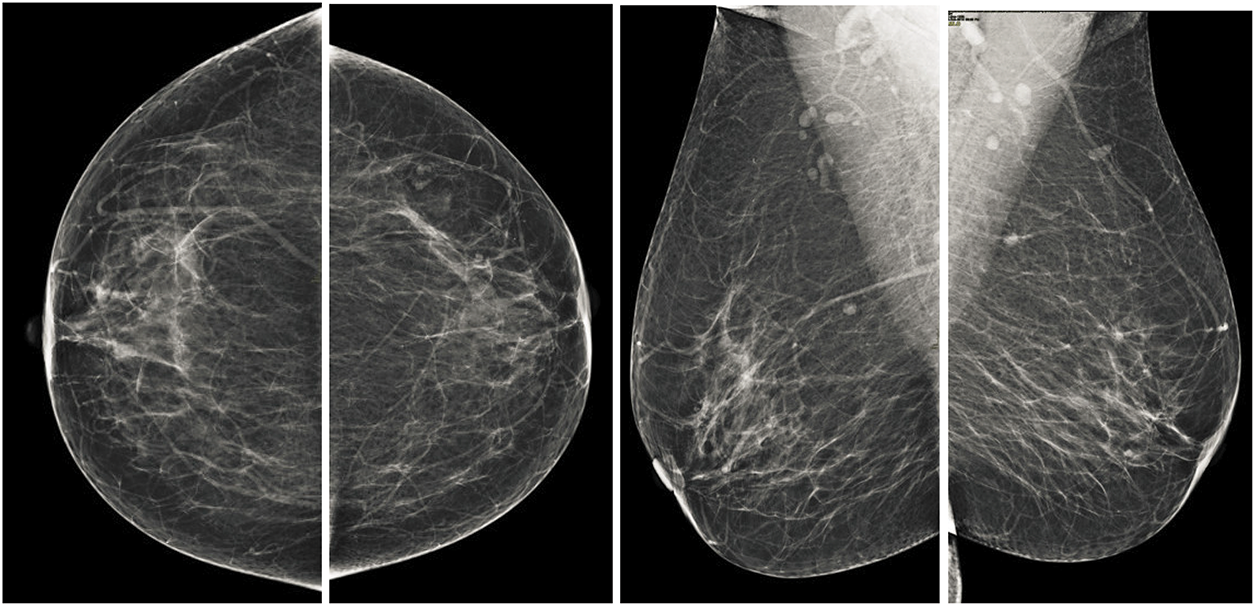

Both the CC and MLO views pose unique challenges, including low contrast and variability in tissue density as shown in the Fig. 2. Despite these limitations, these views often encompass critical diagnostic regions containing malignancies. Consequently, the pectoral muscle’s accurate segmentation and exclusion are essential for isolating the breast area, thereby enhancing the accuracy of subsequent image analyses. Consequently, the accurate segmentation and exclusion of the pectoral muscle are crucial for delineating the breast area, thereby improving the reliability of subsequent image evaluations. Furthermore, the classification of mammographic images based on specific views, in adherence to the BI-RADS framework, facilitates the uniformity of diagnostic protocols. This approach is instrumental for creating automated systems aimed at detecting breast malignancies, improving diagnostic reliability and computational efficiency.

Figure 2: Illustration of standard mammographic perspectives. The first row shows the MLO depiction of the left and right sides, while the second row shows the CC depiction of the left and right sides